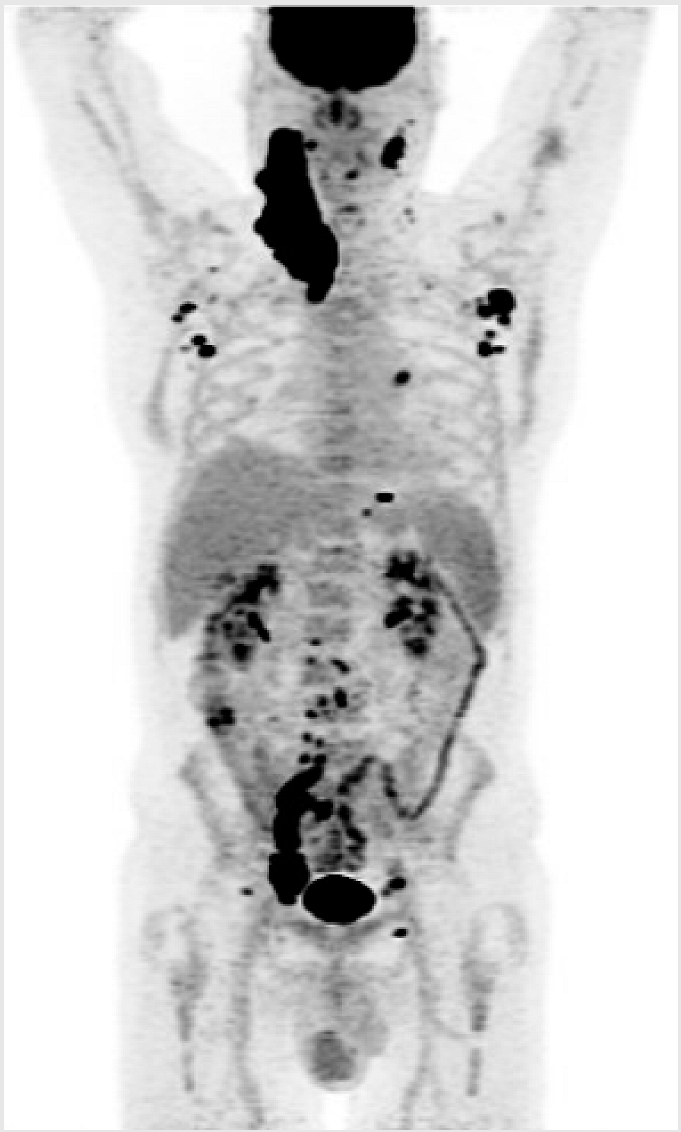

3.1. Illustrative Case 1

Key clinical features

| ![]() |

Key Points for Illustrative Case 1